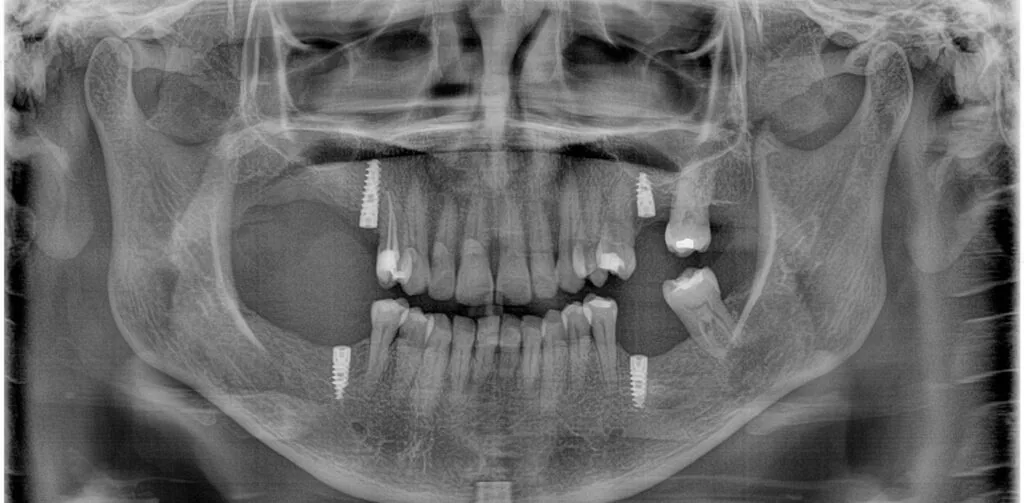

Implantes Dentales

¿Perdiste un diente y no sabes cómo reemplazarlo? ¡La opción de desgastar los dientes vecinos es parte del pasado! Los implantes dentales son una solución fija y segura para reemplazar estos dientes perdidos.

¿En qué consiste?

• La primera parte es la quirúrgica, donde se coloca el implante que se integra al hueso, y

• La segunda es la restauración estética y funcional de la corona del diente.

Trabajo en conjunto con especialistas certificados para asegurar un diagnóstico correcto y planificación precisa.

No todos los pacientes son candidatos, por eso lo más importante es una valoración previa donde podamos ver tus opciones reales.